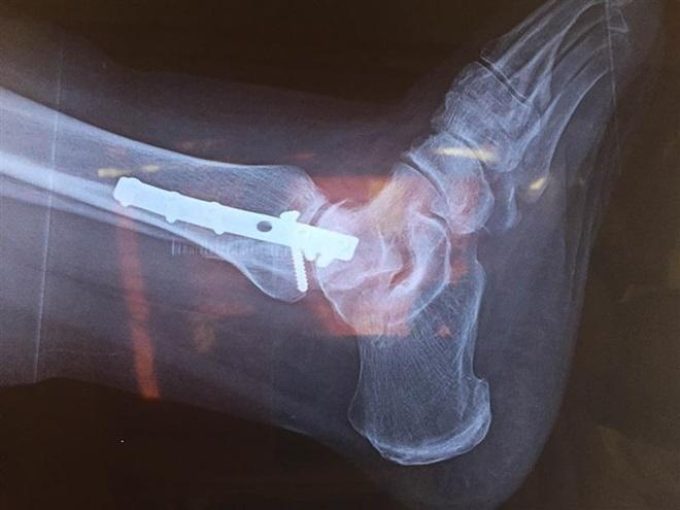

Είναι ενεργό μέλος στην ESSKA (European Society for Sports Traumatology, Knee Surgery and Arthroscopy) και του ICRS (International Cartilage Repair Society). Έχει ειδικότητα σε ΑΘΛΗΤΙΚΈΣ ΚΑΚΏΣΕΙΣ, ΑΡΘΡΟΠΛΑΣΤΙΚΉ ΓΌΝΑΤΟΣ, ΑΡΘΡΟΠΛΑΣΤΙΚΉ ΙΣΧΎΟΥ και ΑΡΘΡΟΠΛΑΣΤΙΚΉ ΏΜΟΥ. Στην ορθοπεδική κλινική, με την υποστήριξη της σύγχρονης τεχνολογίας και την εφαρμογή των πλέον σύγχρονων ιατρικών μεθόδων, αντιμετωπίζει όλο το φάσμα τόσο των επειγόντων, όσο και των χρόνιων ορθοπεδικών παθήσεων. Με τη μέθοδο της ενδομυελικής ήλωσης αντιμετωπίζονται όλοι οι τύποι των καταγμάτων μακρών οστών.